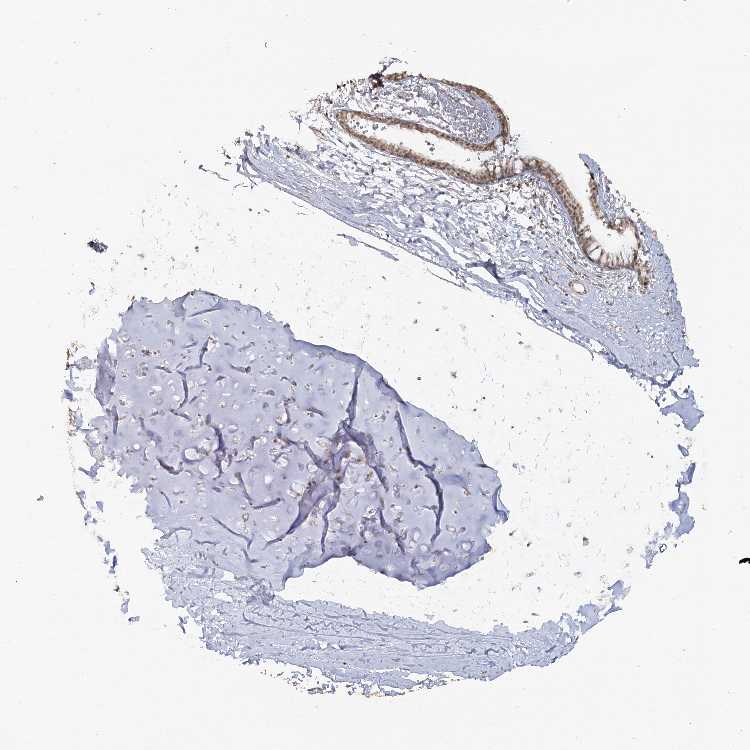

ADIPOSE TISSUE - Antibody stainingi

Antibody staining in the annotated cell types in the current human tissue is reported as not detected, low, medium, or high, based on conventional immunohistochemistry profiling in selected tissues. This score is based on the combination of the staining intensity and fraction of stained cells.

Each image is clickable and will lead to virtual microscopy that enables deeper exploration of all samples and also displays staining intensity scores, fraction scores and subcellular localization as well as patient and tissue information for each sample.

Antibody HPA037980

Adipocytes Medium